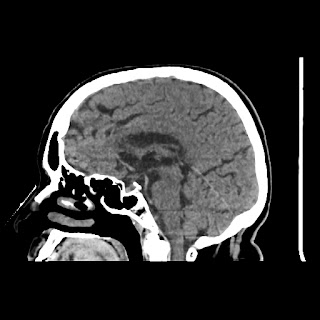

A 75 years old woman with DM-2 since 3 years

Patient O/E images:

C/O: Breathlessness X 2-3 day's

Vomiting 1-2 episode since last night

Cough X 2-3 day's

H/O: unconsiouness since few hour's at home around 10:30 pm

K/C: DM / HTN since 2-3 year's